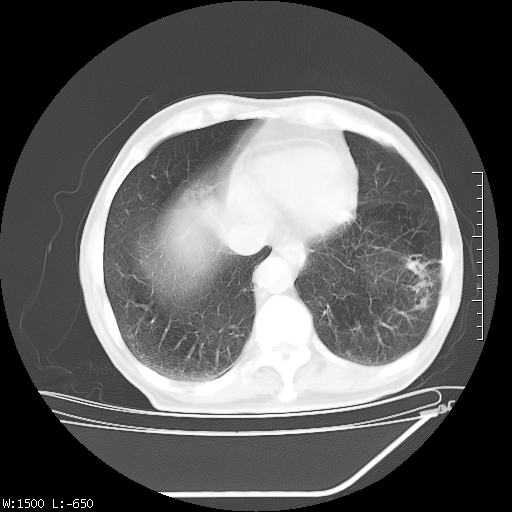

标题: CT23994:男、72、咳嗽、气短两月余,近来消瘦。 [打印本页]

标题: CT23994:男、72、咳嗽、气短两月余,近来消瘦。

右上肺实变,与胸膜关系密切,右肺容积缩小,隆突下淋巴结增大,考虑1 肺结核 2 肺癌

tb可能性大(双肺均可见片状密度增高灶,其内可见低密度空洞)。

右上肺大片状密度增高影,与胸膜关系密切,内见低密度透亮影,胸膜下可见三角形不张影,左下肺沿支气管走形结节影,纵膈内淋巴结显示。考虑结核并疤痕性不张可能性大,建议穿刺活检,排除肺泡癌。